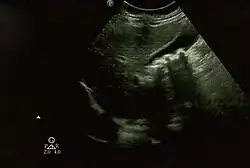

Biliary pseudolithiasis as seen on ultrasonography. The gallbladder contains gallstone mimics resulting from ceftriaxone therapy. |

Biliary pseudolithiasis is an unusual complication of ceftriaxone where the drug complexes with calcium and mimics gallstones.[1][2] It is reversed when ceftriaxone administration is stopped.[2] It was first described in 1988 by Schaad et al. as "reversible ceftriaxone-associated biliary pseudolithiasis".[2][3] Ceftriaxone has been frequently associated with biliary sludge or biliary pseudolithiasis in subsequent reports.[3] Ceftriaxone is excreted primarily through the urine, but also through the bile, up to 40% of its excretion, with concentrations in the bile 20-150 times higher than in the serum.[3][4] It forms a calcium salt in the gallbladder, which can exceed its solubility and create precipitates that resemble gallstones on ultrasonography.[3] The incidence of pseudolithiasis in children treated with ceftriaxone is up to 25%, but most patients are asymptomatic.[3][4] Risk factors for biliary pseudolithiasis include age greater than 24 months, gram-negative sepsis, high doses of ceftriaxone, hypercalcemia, surgery, and decreased bile flow/increased ceftriaxone excretion in bile.[3][4][5] Conservative management with serial ultrasounds is recommended until the "stones" completely resolve.[3] If associated with ceftriaxone, it resolves on average about 2 weeks after the ceftriaxone is stopped.[4]